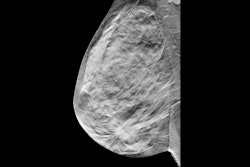

Correlative mammographic, sonographic, and histopathological findings in a 44-year-old woman with a palpable right breast lump. Synthesised 2D mammogram, right breast, mediolateral oblique (MLO) projection: No discrete abnormality is visualised. Interpretation is limited by heterogeneously dense parenchyma (density grade C). All figures courtesy of Dr. Ben Trinh, Dr. Vanessa Atienza-Hipolito, Women’s & Breast Imaging, presented at RANZCR 2025.

Synthesized 2D mammogram, right breast, craniocaudal (CC) projection of the same patient. No mammographic abnormality is identified. Dense fibroglandular tissue (density grade C) reduces sensitivity.